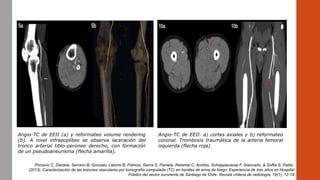

Angio-TC de EEII (a) y reformateo volume rendering

(b). A nivel infrapoplíteo se observa laceración del

tronco arterial tibio-peroneo derecho, con formación

de un pseudoaneurisma (flecha amarilla).

Angio-TC de EEII. a) cortes axiales y b) reformateo

coronal. Trombosis traumática de la arteria femoral

izquierda (flecha roja)

Angio-TC de EEII(a) y reformateo volume rendering (b). A nivel infrapoplíteo se observa laceración del tronco arterial tibio-peroneo derecho, con formación de un pseudoaneurisma (flecha amarilla). Angio-TC de EEII. a) cortes axiales y b) reformateo coronal. Trombosis traumática de la arteria femoral izquierda (flecha roja) Pivcevic C, Daniela, Serrano B, Gonzalo, Latorre B, Patricio, Sierra S, Pamela, Retamal C, Andrés, Schiappacasse F, Giancarlo, & Soffia S, Pablo. (2013). Caracterización de las lesiones vasculares por tomografía computada (TC) en heridas de arma de fuego: Experiencia de tres años en Hospital Público del sector suroriente de Santiago de Chile. Revista chilena de radiología, 19(1), 12-19